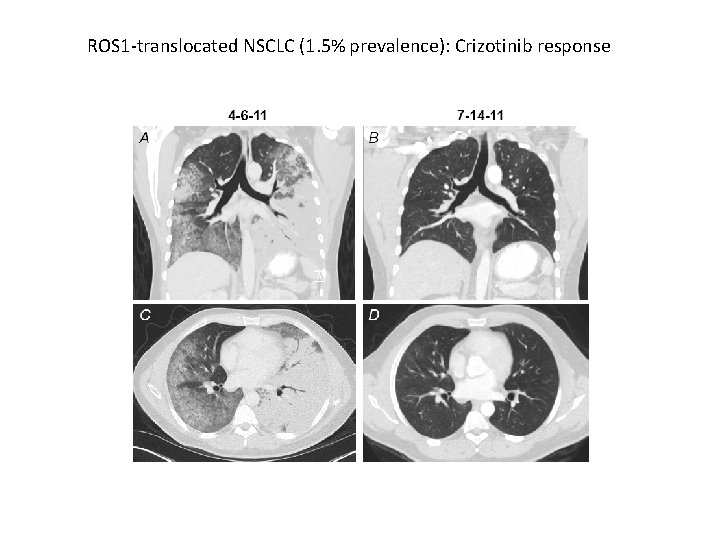

ROS 1 -translocated NSCLC (1. 5% prevalence): Crizotinib response